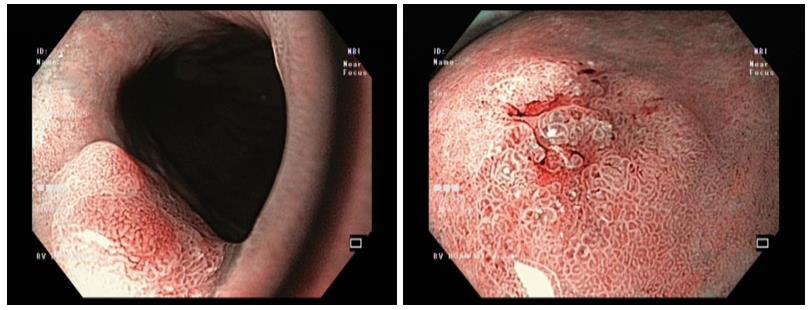

Thông qua hình ảnh nội soi ống tiêu hóa, bác sĩ phát hiện 2 tổn thương trong dạ dày, nghi ngờ ung thư ở giai đoạn sớm – Ảnh: BVCC

Kết quả nội soi phát hiện hai tổn thương bất thường tại dạ dày. Mẫu mô sinh thiết được lấy trong lúc nội soi và gửi đi xét nghiệm giải phẫu bệnh cho kết quả là nghịch sản tuyến độ cao (high-grade dysplasia).

BS.CKI Cao Văn Viễn, Đơn vị nội soi tiêu hóa, cho biết: “Nghịch sản độ cao là một dạng tổn thương tiền ung thư nghiêm trọng. Các tế bào đã có những biến đổi bất thường rõ rệt và có nguy cơ rất cao sẽ tiến triển thành ung thư xâm lấn nếu không được loại bỏ kịp thời. May mắn cho trường hợp của bà Đ., các tổn thương được phát hiện khi vẫn còn ở giai đoạn sớm.

Đây là những tổn thương được phát hiện ở giai đoạn mà các tế bào bất thường vẫn còn khu trú hoàn toàn ở lớp bề mặt (niêm mạc), chưa xâm lấn qua màng đáy để đi vào các lớp sâu hơn chứa mạch máu và bạch huyết. Việc phát hiện ung thư ở giai đoạn sớm giúp nâng cao đáng kể khả năng điều trị khỏi hoàn toàn”.